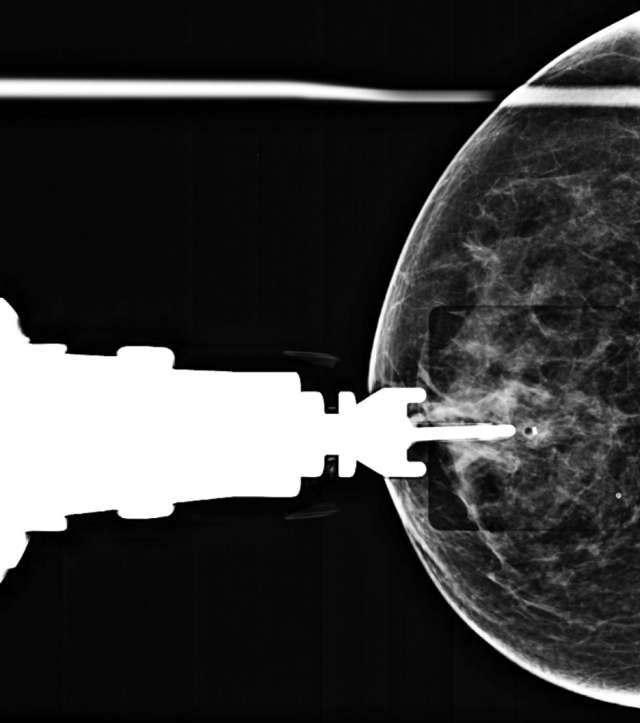

- Technologist takes a stereotactic pair of images (+/- 15 degrees) and radiologist confirms accurate trajectory (Figure 3).

Figure 3. Prefire stereotactic pair of CC images taken +/- 15 degrees.

- Technologist repeats stereotactic pair (+/- 15 degrees) and radiologist confirms accurate trajectory on the postfire images (Figure 4).

Figure 4. Postfire stereotactic pair of CC images taken +/- 15 degrees oblique.